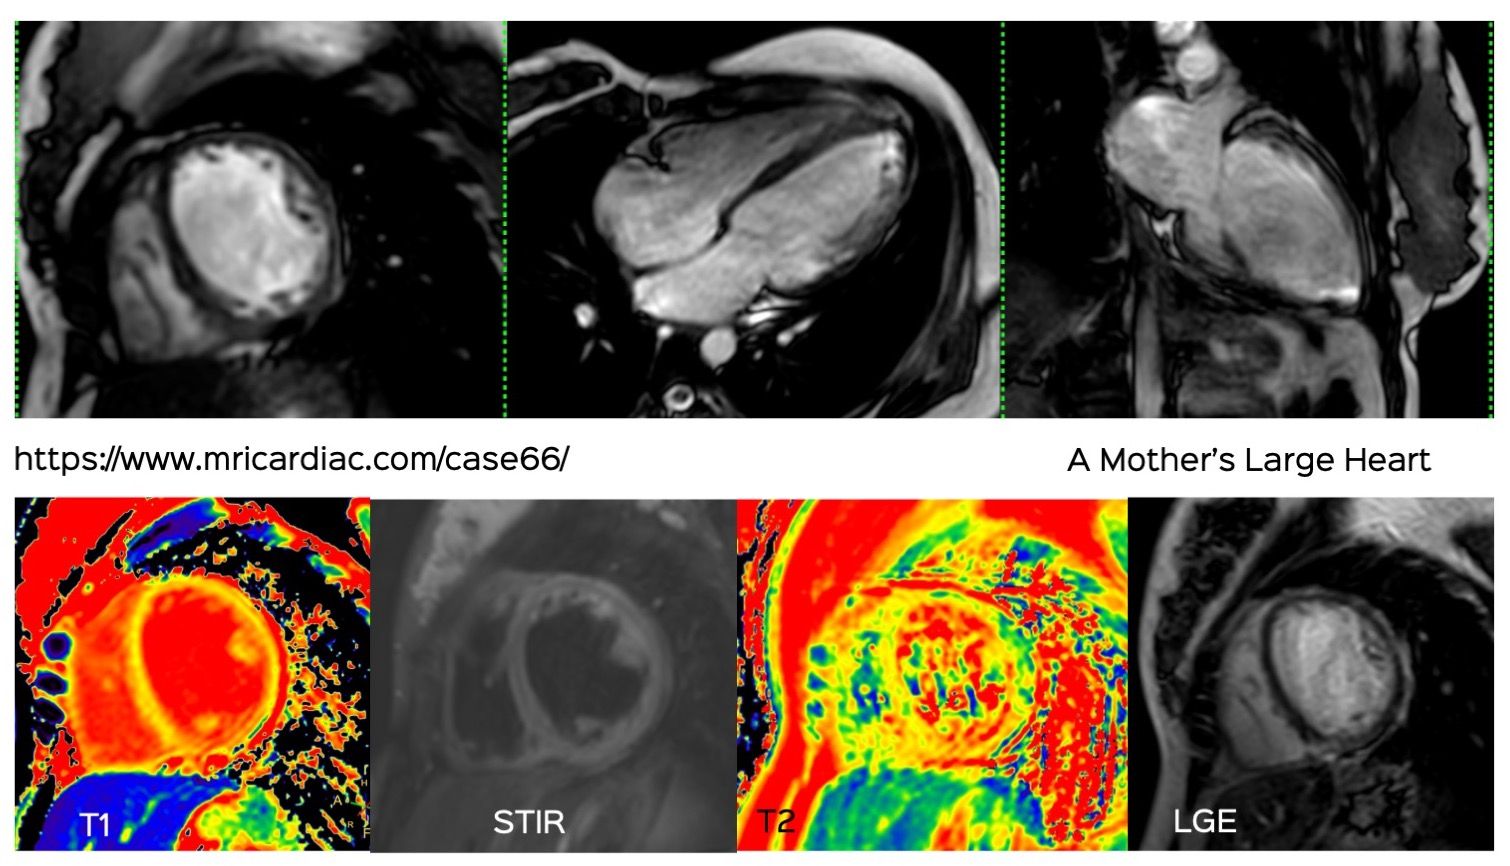

Amyloidosis

Non-Ischemic Cardiomyopathy